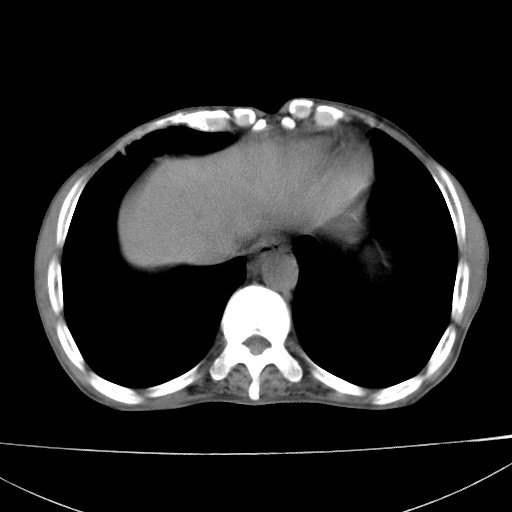

患者 男  41岁,右上腹痛伴腹泻10天,8年前有乙肝,本次b超查肝右叶占位来做ct ,请会诊!

肝硬化\\脾大\\门静脉高压,胃底静脉曲张可能性大.肝右叶肝癌肝内转移,建议增强.左侧小结石.

支持肝癌伴肝内转移,脾大,门静脉高压,胃底静脉曲张。

1)考虑肝癌;建议行ct增强扫描检查。2)脾大,门静脉高压,胃底静脉曲张。3)左肾小结石。

1)考虑肝癌及门脉瘤栓,建议行ct增强扫描检查。2)脾大,门静脉高压,胃底静脉曲张。3)左肾小结石。

结合病史;考虑肝癌。门静脉高压,脾大。胃底静脉曲张。

1)考虑肝癌;2)脾大,门静脉高压,胃底静脉曲张。3)左肾小结石。建议行ct增强扫描检查。